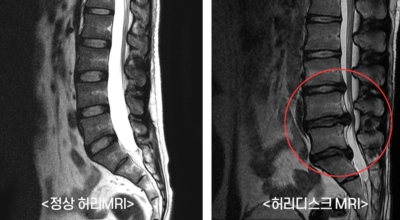

여러 개의 작은 척추뼈가 모여서 척추라는 인체의 기둥을 이루게 되어요. 척추뼈 사이에는 척추뼈끼리 부딪치는 것을 방지하는 쿠션 같은 역할을 하는 '디스크(disc)'라는 말랑말랑한 젤리 같은 구조물이 있는데 우리말로는 '추간판'이라고 하네요.

디스크(추간판)의 한가운데에는 젤리같이 찐득찐득한 '수핵'이라고 하는 성분이 들어 있어요. 그 주변에 수핵을 둘러싸는 '섬유륜'이라 하는 두꺼운 막이 있는데 디스크는 전체적으로 자동차의 타이어와 같은 형태라고 해요. 디스크는 일어선 상태에서는 중력을 받아 납작해져서 바깥쪽으로 약간 볼록한 형태가 된다고 해요.

디스크는 그 특수한 구조 때문에 웬만한 힘이 가해져도 효율적으로 쿠션 역할을 할 수 있겠습니다. 그러나 갑작스럽게 무거운 물건을 들어 올리거나, 부자연스러운 자세를 장시간 취하면 디스크에 무리한 힘이 가해지면서 디스크가 밖으로 돌출이 되게 돼요. 심한 경우 디스크를 감싼 막이 터지면서 그 안에 있는 수핵이 튀어나오게 돼요. 디스크는 대부분이 후방이나 후외방으로 돌출되는데 이 경우에 바로 곁에 있는 신경을 누르게 된다고 해요.